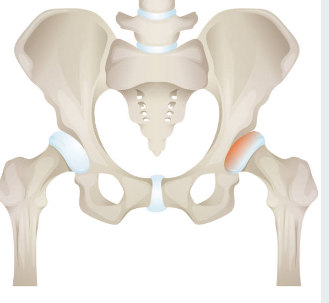

고관절 골절이란?

골다공증과 같은 뼈 약화 상태 또는 외상으로 인해 발생하는 대퇴골(허벅다리 뼈) 상단의 골절을 의미하는 것입니다. 일반적으로 낙상이나 직접적인 충격으로 인해 발생하며, 특히 고령자에서 흔히 일어날 수 있는 사고입니다. 고관절 골절치료는 주로 수술과 재활이 필요하며, 이는 환자의 이동과 삶의 질에 많은 영향을 미칠 수 있습니다.